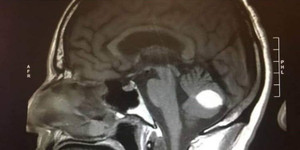

Người đàn ông ở Phú Thọ có biểu hiện trí nhớ suy giảm, không tìm được cảm giác thăng bằng khi đi bộ, dùng thuốc uống tại nhà không đỡ.